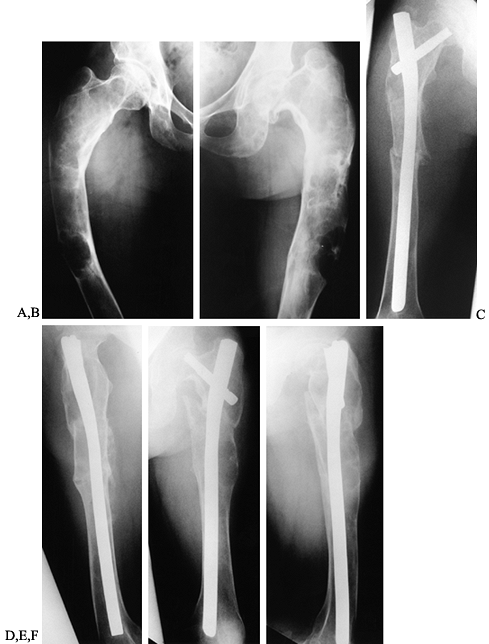

![]() |

|

Figure 127.10. AP (A) and lateral (B)

radiographs of the right knee show a radiolucent lesion in the lateral tibial epiphysis, which extends from the growth plate to the subchondral bone. In this case, there is no stippled calcification, but this location is typical for a chondroblastoma in this age group, and biopsy confirmed this. Frontal plate (C) and cross-sectional (D) MRI images nicely delineate the extent of this lesion within the epiphysis. On the frontal plate image, surrounding edema of the epiphysis is evident. In the axial image, there is a central dark area that represents mineralization within the lesion. |